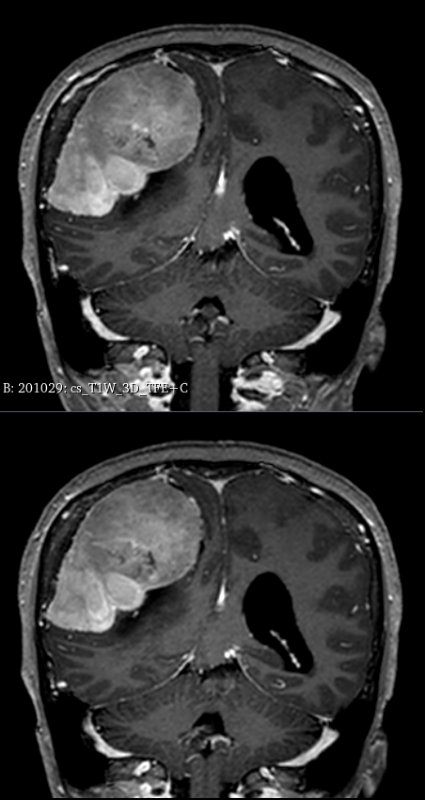

据悉,该患者因“间断头痛4年、加重伴头晕4个月”就诊。头颅MRI检查显示,其右侧顶部巨大占位紧邻中央沟功能区及上矢状窦等重要血管。

术前精准建模:运用3D Slicer软件整合多模态影像数据重建三维模型,清晰呈现肿瘤与周边功能区、血管的空间关系,为手术规划提供精准数字化依据。